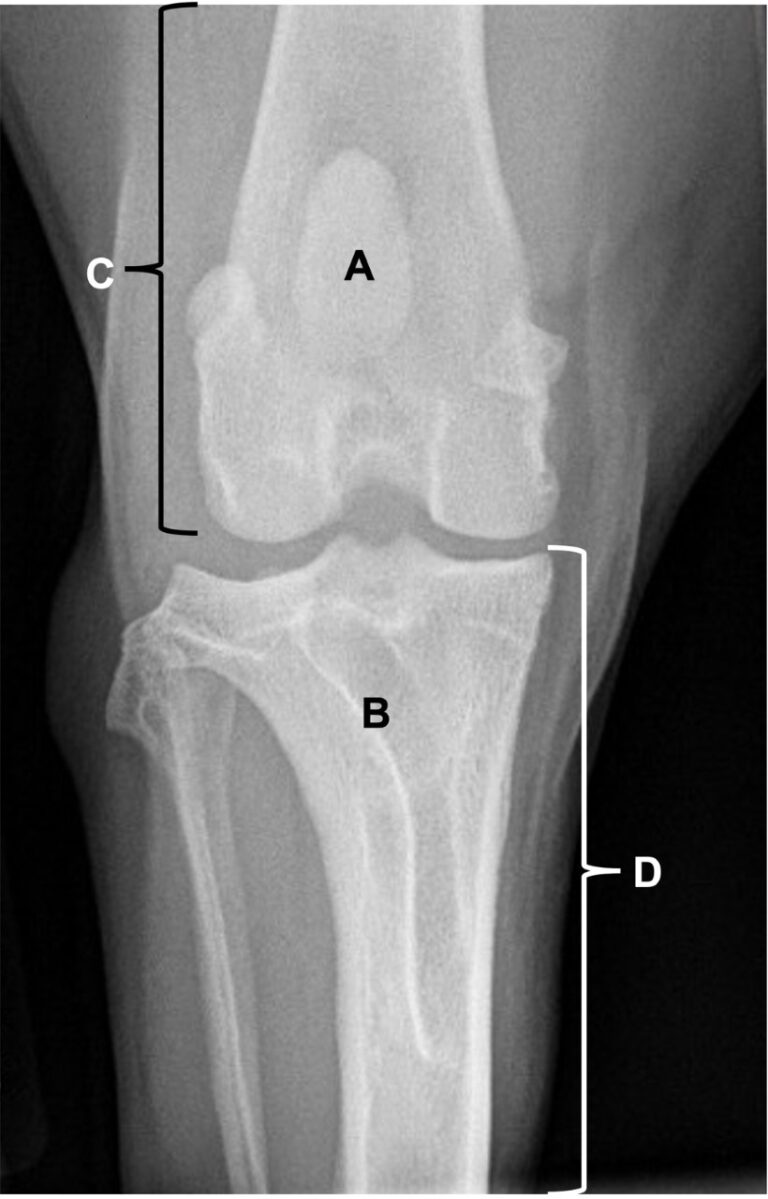

Pourquoi les coûts d'une opération pour chien varient-ils ? Les prix des vétérinaires sont fixés par chaque praticien Elle se trouve dans une gouttière, appelée la trochlée, qui lui permet de coulisser de bas en haut le long du fémur, sans s'écarter à gauche et à droite Pourquoi le prix des opérations d'un chien varient-elles ? D'une manière générale, les prix des consultations pour les chiens varient d'un